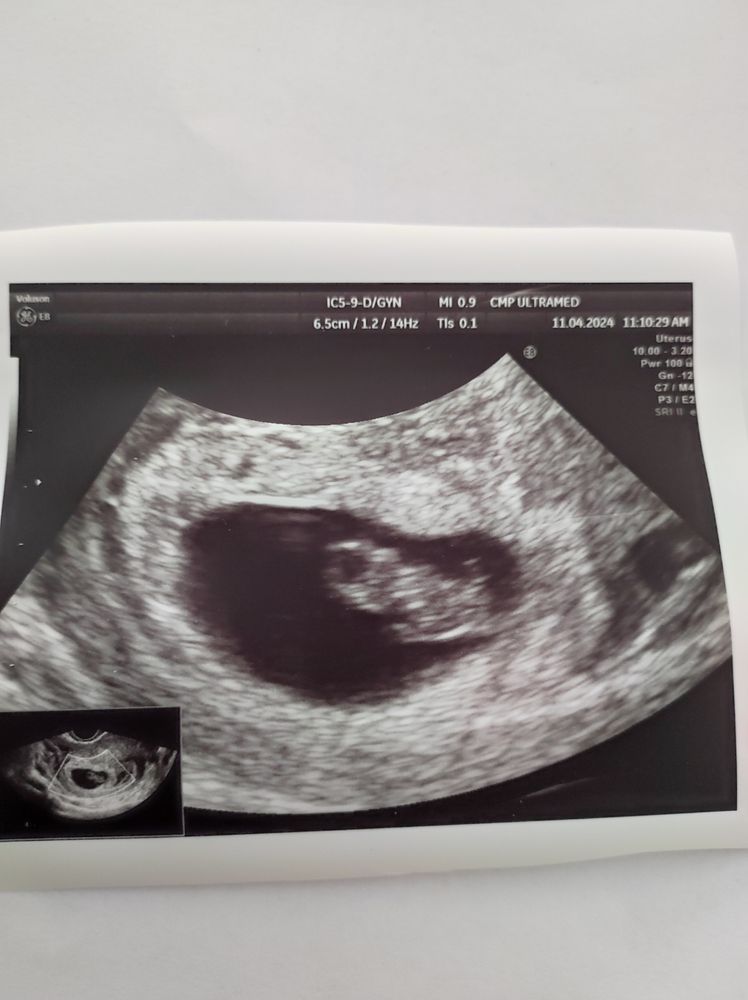

Второе УЗИ на сроке 7 и 6 (по месячным)

УЗИ, КТГ, доплерУра, мы дожили до приема у Черемушкиной :) И у нас всё отлично, отпустили до 13 мая (OSCAR). Только нагрузки ограничили - из-за кольцевидного хориона, как я поняла. Но я надеюсь всё-таки в бассейн или на ЛФК по чуть-чуть походить, без фанатизма разрешили. Иначе я к родам опять 20 кг наберу и буду на коляске ездить из-за артроза - уже и так болевой синдром имеется, хотя не прибавила нисколько.

Срок по КД сейчас 7 и 6, по УЗИ 7 и 5 (Hadlock).

По методу Рамзи вроде похоже на девочку. Нам неважно, просто любопытно и делать нечего месяц, будем гадать 😁